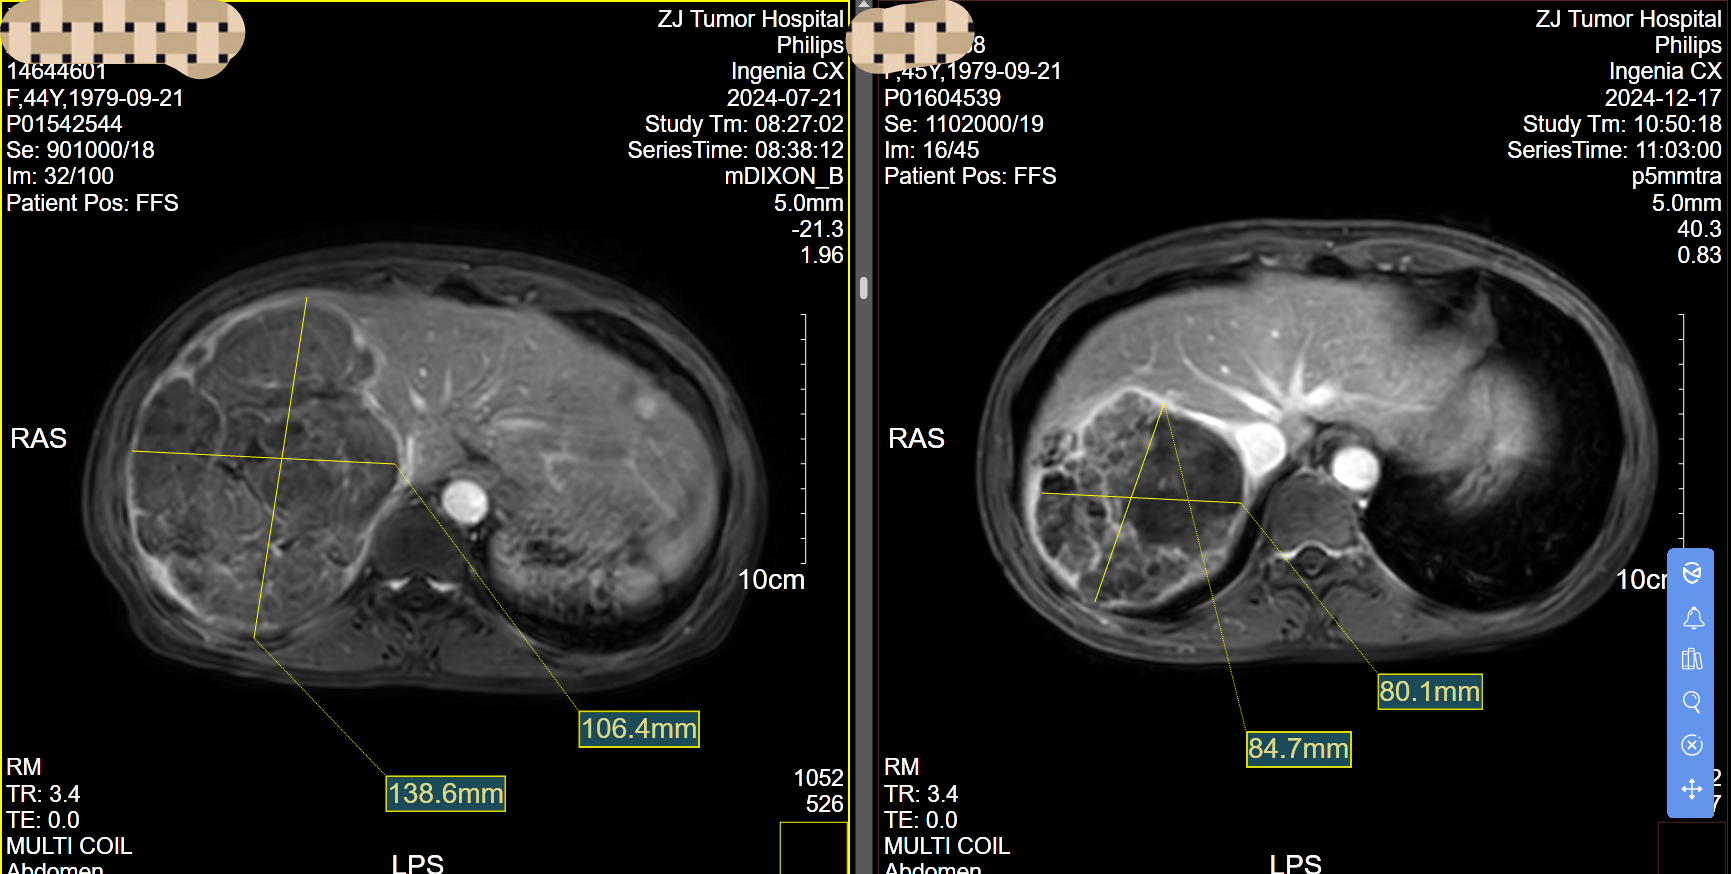

經(jīng)橈動脈/肱動脈Tace+haic治療晚期肝惡性腫瘤1例!45歲女性,發(fā)現(xiàn)時肝腫瘤巨大,無外科手術(shù)機會。經(jīng)過介入科與肝膽外科通力協(xié)作,經(jīng)過3次經(jīng)橈動脈(前兩次)/肱動脈(第3次)tace+haic治療后,腫瘤明顯縮小,腫瘤指標明顯下降,預計再做一次即可轉(zhuǎn)化外科手術(shù)成功。無法切除手術(shù)巨快肝癌患者,經(jīng)橈動脈/肱動脈tace+haic治療,療效確切,副反應(yīng)少,外科手術(shù)轉(zhuǎn)化率高(文獻報道60%),術(shù)后無需長期臥床,康復快速,是晚期巨快肝惡性腫瘤的治療優(yōu)選!浙江省腫瘤醫(yī)院介入科,文頌副主任醫(yī)生,每周四下午專家門診![強][強][強][強][強][強]精選最優(yōu)肝癌治療策略,這里有!